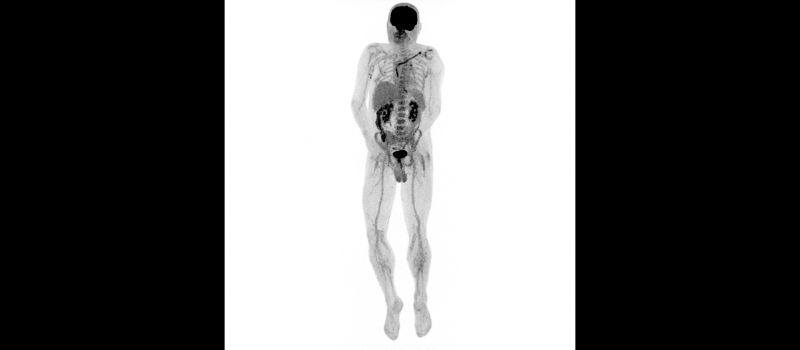

Kontrolní TEE na našem pracovišti potvrdila vlající vegetace v pravostranných srdečních oddílech – největší o velikosti 25×9 mm, menší přisedlý útvar s rozměrem 7×9 mm. Provedené PET/CT bylo v korelaci se suspektními zánětlivými změnami téměř v celé délce elektrod. V rámci multidisciplinárního týmu bylo vzhledem k velikosti vegetací a rizikovým faktorům rozhodnuto o kardiochirurgické extrakci stimulačního sysému. Transvenózní extrakce představovala větší riziko s nejasným výsledkem - možné embolizace do plic, mechanické komplikace s ohledem na stáří elektrod a známý uzávěr levé v. subclavia. Předoperační přípravu zkomplikovala hluboká žilní trombóza vlevo, která vedla k odkladu výkonu. Začátkem srpna pacient podstoupil kardiochirurgickou extrakci celého systému. Vlastní výkon i pooperační průběh byl bez komplikací a pacient byl přeložen zpět do spádové nemocnice k pokračování antibiotické léčby.